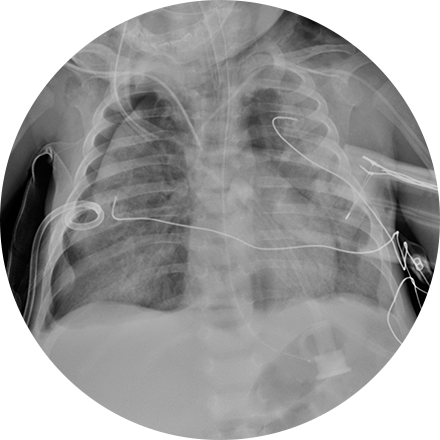

X-ray is the oldest and most economical form of medical imaging. During the procedure, radiation passes through the body onto “film” (now digitized and displayed on a computer screen). In neuroimaging, spinal X-rays are used to assess for the degree of spinal motion with flexion or extension.